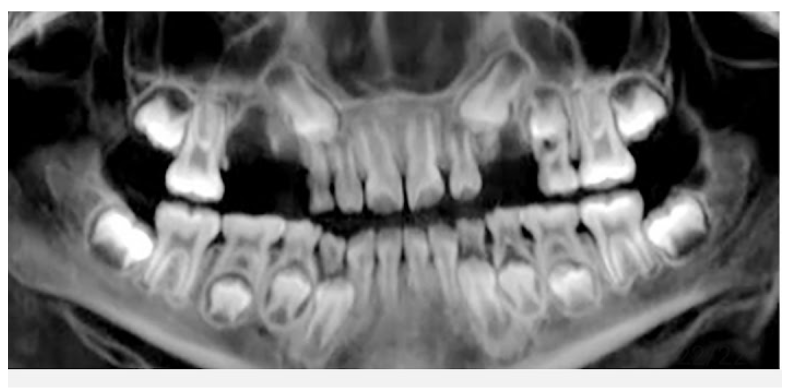

1.Lower adult CI there? YES. so def 6-7

1. Upper adult CI there (they normally erupt 7-8)? NO, baby ones should shed at 6-7.

Conc: pt. Is 6 y.o